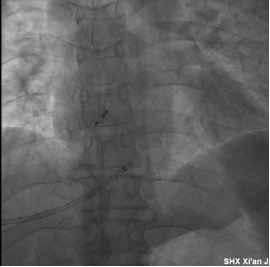

随后,魏峰副主任医师保留穿刺导丝后,护送患者到达介入手术室,在王海燕主任与肖娟护士长的统一协调下,介入手术室早已做好了准备,18:20分手术正式开始,在王海燕主任与张玉顺教授的指导下,何璐主治医师、王星烨主治医师、魏峰副主任医师密切配合,顺利完成了经肝静脉PFO封堵术(图3),随后消化内科马福权主治医师与魏峰副主任医师密切合作,顺利完成了经颈静脉穿刺路径对经皮肝静脉穿刺伤口的栓塞与封堵处理。整个手术过程历时两个半小时,手术安全、顺利。

图3经肝静脉成功封堵PFO